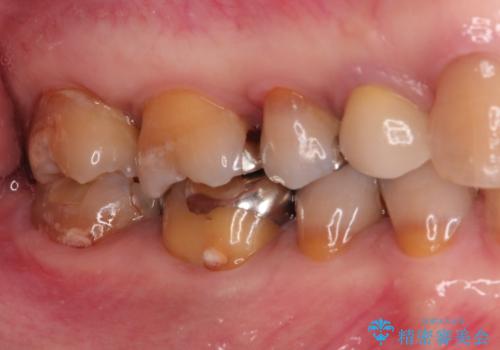

- 他院で入れたセラミックインレーがかけたことを主訴に来院されました。

他の部位にもむし歯を認めたため、優先度の高い歯から治療を行っております。

咬合力が強くかかる部分には欠けるリスクのほとんどない金属を用いることが最良ですが審美性に劣ります。

今回は白い材料での修復を希望されたため、欠けるリスクが高いセラミックインレーは避け、セラミッククラウンにて治療を行いました。